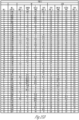

- FIGS. 28A-28D illustrate table of the results of an example of the MID immunoassay for individual synovial fluid samples testing ⁇ -defensin positive and culture negative (+/-)

- FIGS. 29A-29D illustrate a table of an example of the MID immunoassay for individual synovial fluid samples testing ⁇ -defensin negative and culture negative (-/-).